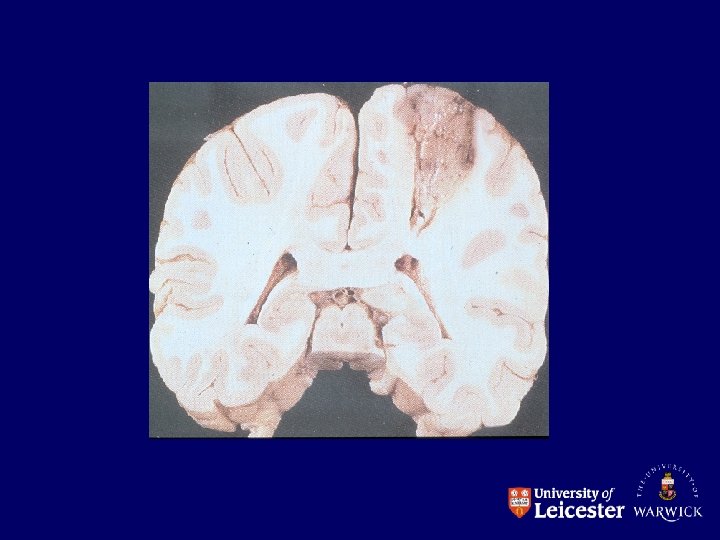

Thrombosis • Definition Thrombosis is the formation of a solid mass of blood within the circulatory system

Effects of thrombosis • Arterial – ischaemia – infarction – depends on site and collateral circulation • Venous – – congestion oedema ischaemia infarction

Coronary artery thrombosis